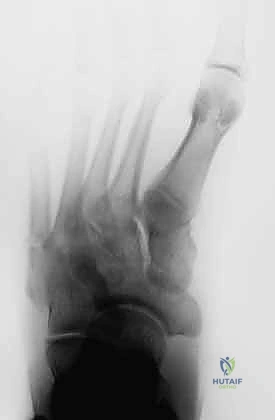

لنبداً بتحديد ما نتعامل معه بالضبط. كسر جونز هو إصابة حادة تحدث في العظمة الخامسة من مشط القدم (Metatarsal Bone)، وهي العظمة الطويلة التي تقع على الحافة الخارجية للقدم وترتبط بإصبع القدم الصغير. سُمي هذا الكسر بهذا الاسم نسبة إلى جراح العظام البريطاني السير "روبرت جونز" الذي وصفه لأول مرة في عام 1902 بعد أن أصيب هو شخصياً به أثناء الرقص!

السبب الذي يجعل كسر جونز سيئ السمعة في عالم جراحة العظام هو موقعه الدقيق. يحدث الكسر في منطقة تُعرف باسم المشاش (Metaphyseal-Diaphyseal Junction). هذه المنطقة تحديداً تعاني من ضعف شديد في الإمداد الدموي، وتُعرف طبياً باسم منطقة ضعف التروية (Watershed Area). وكما نعلم، الدم هو الناقل الأساسي للأكسجين والعناصر الغذائية والخلايا البانية للعظم؛ وبدون تدفق دموي كافٍ، تصبح عملية التئام الكسر بطيئة للغاية، وترتفع احتمالات عدم الالتئام (Non-union) أو تأخر الالتئام (Delayed union) بشكل كبير إذا لم يتم التدخل بشكل صحيح.

- التصوير بالأشعة السينية (X-rays): هي الخطوة الأولى والأساسية. يتم أخذ صور بأوضاع مختلفة (أمامية، جانبية، ومائلة) لتحديد موقع الكسر وشكله بدقة.